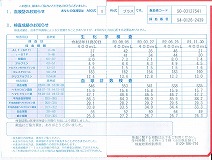

0140 健康診断結果

0109 24.7.29健康診断=pdf

0108 ①22.8.23荒尾市民病院=pdf ②2023-08-21健康診断結果.pdf 8/10(木)受診 荒尾市民病院